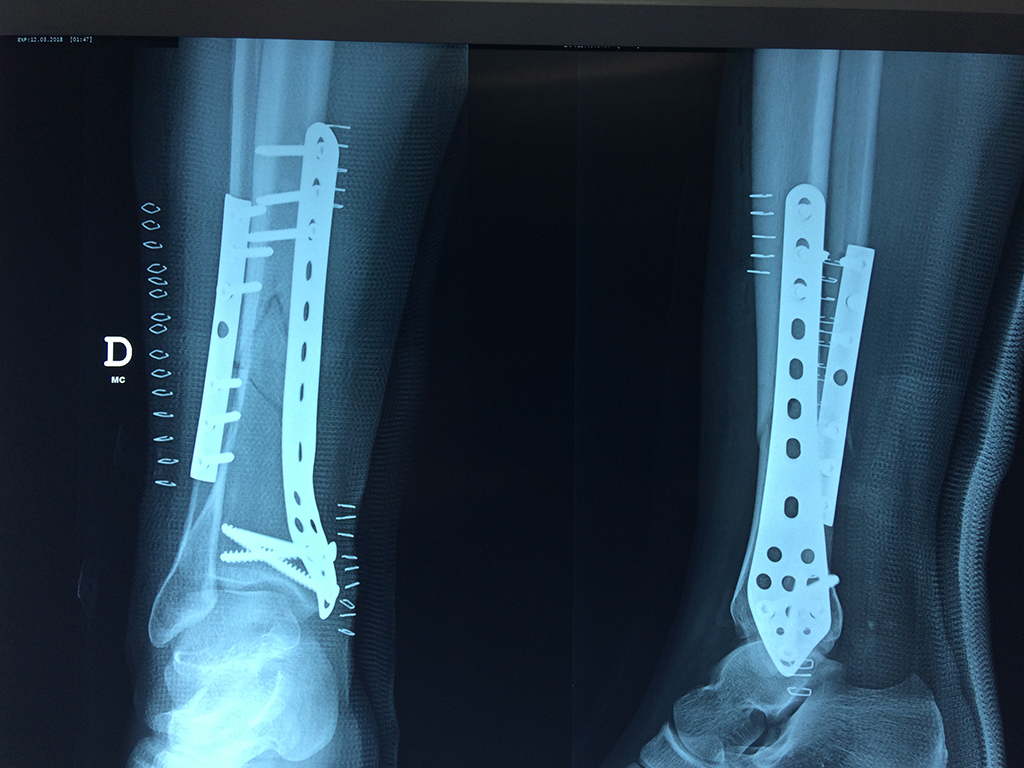

Cirugías de Codos - Perone y Tibia

Aunque cada uno de estos huesos puede fracturarse por separado, normalmente la rotura es una lesión que se produce de forma conjunta

La mayor parte de las roturas implican a la parte proximal del hueso (parte del hueso próximo a la rodilla) o a la parte distal (parte del hueso cerca del tobillo).

Debido a la fina cobertura de piel que recubre la tibia y el peroné, las fracturas generalmente son abiertas, es decir, el hueso roto rasga la piel, atravesándola. Las fracturas de tibia y peroné generalmente se producen por un fuerte impacto o torsión.